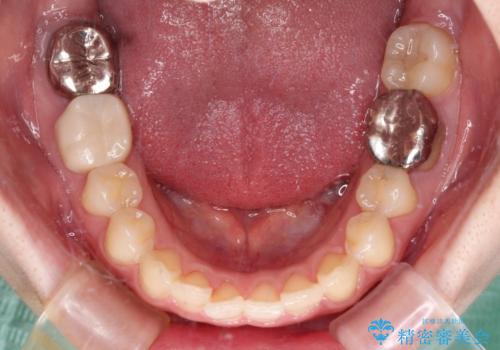

デコボコ歯列をきれいに インビザラインによる矯正治療

- 上下歯列全体のデコボコを気にして来院された患者様です。

主に下顎歯列全体の後方移動とIPR(歯と歯の間を削る)によってデコボコが解消するように設計し、インビザラインにより治療を行うこととしました。